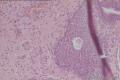

尿道口肿物

性别

女

年龄

50

标本名称

大体所见

灰白组织2块,体积0.5*0.5*0.3立方厘米。

尿道肉阜